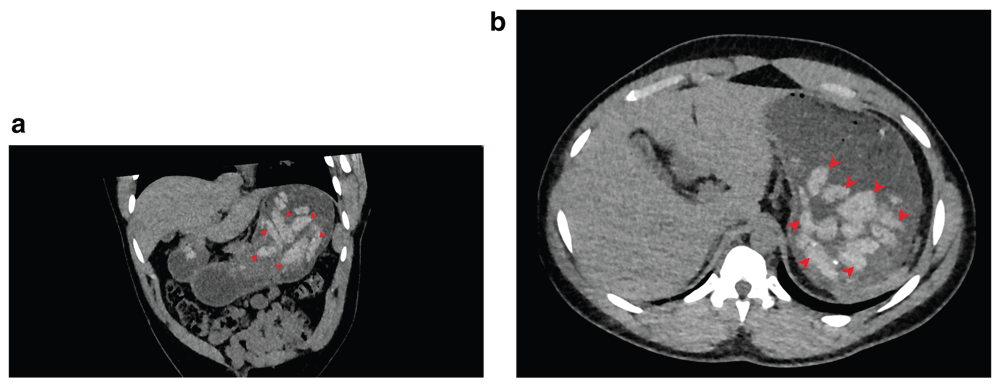

This case involved a young and healthy man from western Africa whom the police arrested for possession of cocaine in the street of Geneva, Switzerland. Police officers also suspected him of having swallowed cocaine pellets and brought him in November 2018 to our Emergency Department (ED) for investigation of bodystuffing. A low-dose abdominal CT scan was done, showing multiple foreign bodies of similar appearance in the stomach, which the on-call radiologist reported to be compatible with ingested drug packets (Figure 2a and 2b).

(a) Multiple intra-digestive foreign bodies (arrows) located in the stomach and the first part of the duodenum (oblique coronal view). (b) Multiple intra-digestive foreign bodies (arrows) in the stomach (axial view).

In accordance with our guidance on the clinical management of bodystuffing, the patient was subsequently admitted to our secured hospital inpatient ward for observation. Upon his admission to the ward, he continued to deny the ingestion of drug packets and revealed that he had consumed ‘fufu’ the previous evening. Indeed, his eating habits included only one meal a day, and this was usually a heavy starchy dish from western and central Africa called ‘fufu’. Eating fufu left him feeling full for a whole day without the need of eating again. This critical information was passed onto the radiologist who carefully reviewed the images with the attending supervisor: the foreign bodies, which were previously read as compatible with images of drug pellets, were in the process of being digested! In fact, the CT scan showed images of foreign bodies with irregular borders and of different sizes (Figure 3a and 3b). Drug pellets have clearly defined and regular edges, and, if mechanically manufactured, they would have been of the same size and shape. The continuous denial of bodystuffing by the patient, his mention of fufu, the revised radiological reading, combined with the absence of acute signs of cocaine or heroin being released from dissolving bodystuffed packets were compatible with the patient’s history of fufu intake. We immediately informed the criminal justice authorities and the patient was rapidly discharged from our secured hospital inpatient ward.